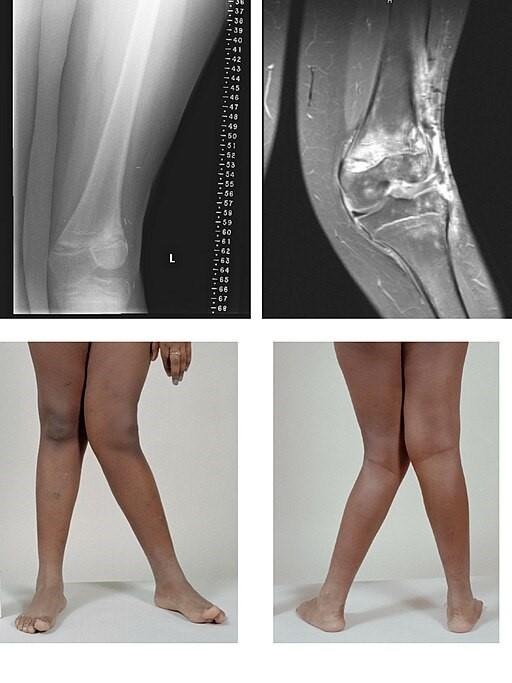

El término médico para las rodillas valgas es "genu valgum": genu significa "rodilla" en latín, y valgum significa "doblada hacia fuera". En las rodillas valgas, si las rodillas se tocan es la parte inferior de la pierna la que parece doblada hacia fuera. Por tanto, si tienes rodillas valgas, no puedes estar de pie con las rodillas Y los tobillos juntos.

A medida que los huesos de las piernas del niño crecen y se desarrollan, tienden a adoptar una forma "patizamba". Ahora, si sus rodillas están juntas, sus pies y tobillos están separados. Suele ser más evidente en torno a los 3 ó 4 años, y suele mejorar gradualmente hasta alcanzar la posición correcta a medida que el niño permanece de pie durante más tiempo. Las rodillas valgas son normales hasta los 7 u 8 años, aunque pueden durar más tiempo.

Por BioMed Central, CC BY 2.0, vía Wikimedia Commons

El diagnóstico de las rodillas valgas puede hacerse con sólo mirar al niño. Si es especialmente grave o se produce fuera del intervalo de edad normal, puede ser necesario realizar más pruebas. Por ejemplo, radiografías o análisis de sangre.

La gravedad de las rodillas valgas puede evaluarse midiendo la distancia entre los tobillos cuando el niño está de pie con las rodillas juntas o midiendo otros ángulos de las piernas.